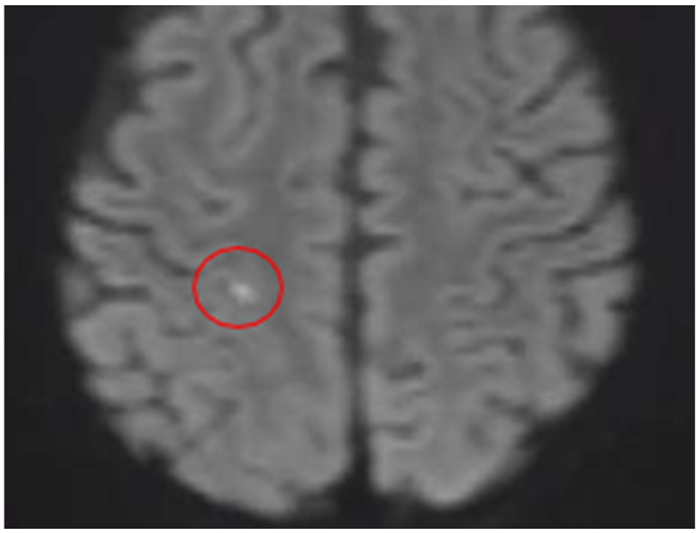

Quadrant A: DWI sequence

|

| A Minimal Right Subcortical Postcentral Parietal Hyperintensity Is Observed This shows restricted diffusion and signal drop on the ADC map Consistent with a Hyperacute Ischemic Focus